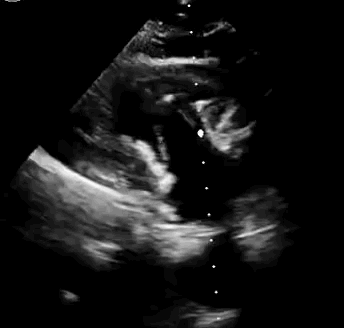

本次臨床前研究經(jīng)右側頸靜脈置入LuX-Valve Plus輸送系統(tǒng)可調彎鞘管,在DSA及超聲引導下將人工三尖瓣瓣膜植入到原有三尖瓣位置,利用獨特的錨定技術將人工瓣膜支架可靠固定在預定的位置。

上海中山醫(yī)院葛均波院士、錢菊英院長、周達新教授、潘文志教授、潘翠珍教授、李偉教授共同完成此次臨床前研究。術后葛均波院士對Lux-Valve Plus的器械操作性能給予了高度評價,DSA和超聲影像也顯示出在本次研究中Lux-Valve Plus的安全性和有效性俱佳。